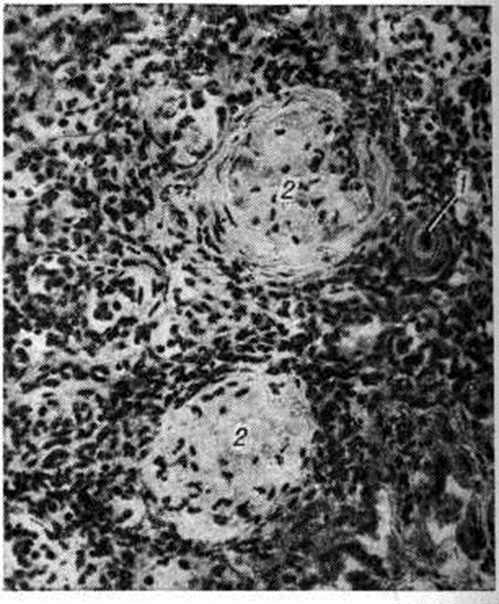

Рисунок 2.

Микропрепарат центральной артериолы селезёнки при гиалинозе: 1 — стенка артериолы (в центре рисунка) представлена гомогенными гиалинизированными массами (окраска гематоксилин-эозином; × 200); 2 — фиксация фибрина в гиалиновых массах артериолы (светлое кольцо). Обработка антифибринной сывороткой, прямой метод Кунса; × 140.

Гиалиноз наблюдается в соединительной ткани, строме органов и стенке сосудов (рисунок 2) в исходе плазматического пропитывания, фибриноидного набухания, склероза, хронический воспаления, некроза. В исходе плазматического пропитывания возникает Гиалиноз сосудов, чаще в артериальной системе. Наиболее распространён Гиалиноз мелких артерий и артериол (смотри Артериолосклероз). Гиалиноз артериол возникает в результате повреждения эндотелия, аргирофильных мембран и гладкомышечных волокон и пропитывания стенок сосуда белками плазмы крови, которые затем подвергаются ферментативным воздействиям, коагулируются и уплотняются, превращаясь в гиалиноподобное плотное вещество. Гиалиновые массы оттесняют кнаружи и разрушают эластическую пластинку, что ведёт к истончению средней оболочки; в результате артериолы превращаются в утолщённые плотные трубочки с резко суженным или полностью закрытым просветом. Гиалиноз мелких артерий и артериол, носящий системный характер, но наиболее выраженный в почках (рисунок 3 и 4), головном мозге, сетчатке глаза, поджелудочной железе, коже (рисунок 5), особенно характерен для гипертонической болезни (гипертонический артериологиалиноз). Нередко системный Гиалиноз артериол и мелких артерий наблюдается при хронический васкулярном гломерулонефрите и симптоматической артериальной гипертензии любого генеза. Распространённый Гиалиноз артерий эластического и эластическо-мышечного типов постоянно наблюдается при атеросклерозе, диабете и отражает процессы плазморрагии и инсудации, характерные для этих заболеваний. Местный Гиалиноз артерий как физиологическое явление встречается в селезёнке взрослых и пожилых людей, отражая функционально-морфологически особенности селезёнки как органа депонирования крови.